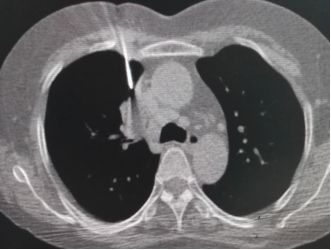

左侧下肢肿胀半月伴急性呼吸困难3天,CT和DSA造影检查发现肺内可见大块血栓,诊断为肺栓塞。

经植入下腔静脉滤器,肺动脉置管溶栓后,肺动脉内血栓消失。